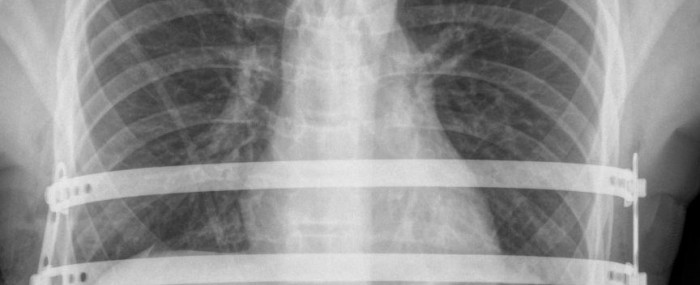

The only treatment is surgery, involving a procedure to implant a molded metal prosthesis behind the sternum so as to push it forward. Before the locally produced implant was developed, surgeons used an imported stainless steel device with serrated edges and two stabilizer bars, but these were not always effective and the bars could move, compressing mediastinal structures such as the heart and large blood vessels. “This displacement is dangerous,” Tedde said.

The Brazilian implant, which has been patented, is made of titanium, an element that is chemically and biologically more compatible with the human body, reducing the occurrence of allergic reactions. The bars have smooth extremities, and the stabilizers are oblique with pressure screws for anchoring. “I combined good ideas with solutions that had already been validated to create a better device that makes the procedure safer,” Tedde said.

The procedure is minimally invasive thanks to video-assisted thoracoscopy, with a lateral incision (formerly frontal and then median). The length of hospital stay has been reduced thanks to the Brazilian implant, falling from seven to five days for the first 30 patients in the project, and to four days for the next 20.